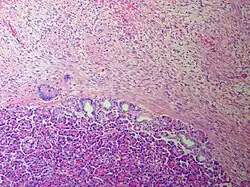

Niezależnie od postaci klinicznej guzy desmoidalne cechują się tym samym obrazem makroskopowym i mikroskopowym, choć guzy położone poza jamą brzuszną są mniejsze[17]. Makroskopowo guzy są przytwierdzone do mięśnia lub powięzi. W momencie rozpoznania większość zmian osiąga wielkość 5–10 cm, choć możliwe są nawet mierzące 20 cm guzy[17][2][3][29]. Guz jest lity i twardy, na przekroju koloru szarobiałego o lśniącej powierzchni z obecnym grubym beleczkowaniem, może przypominać bliznowca[3][30][2]. Guz desmoidalny makroskopowo nacieka sąsiednie tkanki[2], ale w obrębie jamy brzusznej guzy mogą wydawać się dobrze odgraniczone[3].

Mikroskopowo guz jest zbudowany z wydłużonych, smukłych komórek wrzecionowatych o jednolitej morfologii nie wykazujących cech atypii. Komórki wrzecionowate budujące utkanie guza desmoidalnego posiadają małe, blade i ostro odgraniczone jądro komórkowe z jednym lub kilkoma jąderkami. Komórki są otoczone zrębem kolagenowym z dobrze widocznymi naczyniami[2]. Komórki i włókna kolagenu są ułożone w wiązki, które jednak nie są tak wyraźnie zaznaczone jak we włókniakomięsaku[2][3]. Utkanie guza wykazuje pewne zróżnicowanie pod względem komórkowości[2], indeks mitotyczny waha się w dość szerokich granicach[3]. Czasem podścielisko składa się z wiązek kolagenu przypominające bliznowiec[2]. Guz jest słabo odgraniczony i penetruje do sąsiednich tkanek[2].